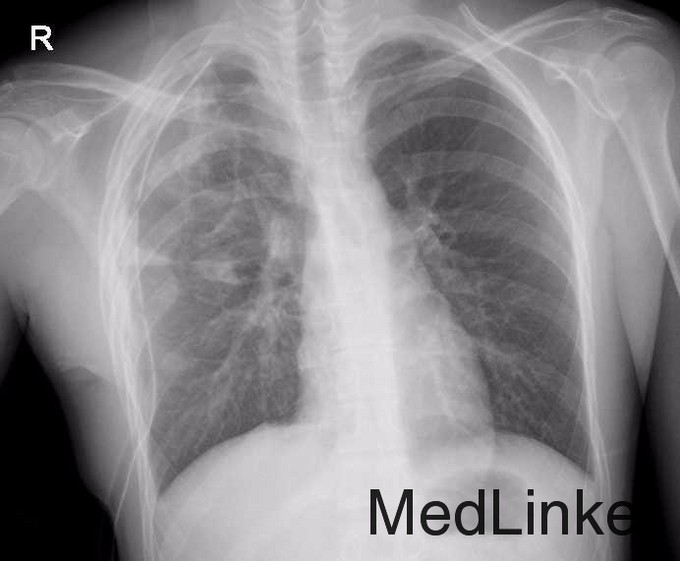

气胸x线胸片表现

气胸x线胸片表现,气胸x线胸片典型表现

查体 辅查 胸片示:右侧气胸.

气胸x线胸片典型表现

气胸x线胸片报告

气胸图片 x线

气胸的x线影像描述

正常胸片和气胸胸片

气胸x线

气胸x线胸片

典型气胸x线胸片图解

气胸x线胸片图解

气胸胸片典型图片

气胸的x线表现

气胸x线胸片图解x光片

气胸x线胸片特征

气胸x线胸片图解胸廓

气胸的x线表现图片

正常胸片与气胸胸对比

气胸胸片典型

气胸胸片

气胸胸片怎么看

气胸胸片图解